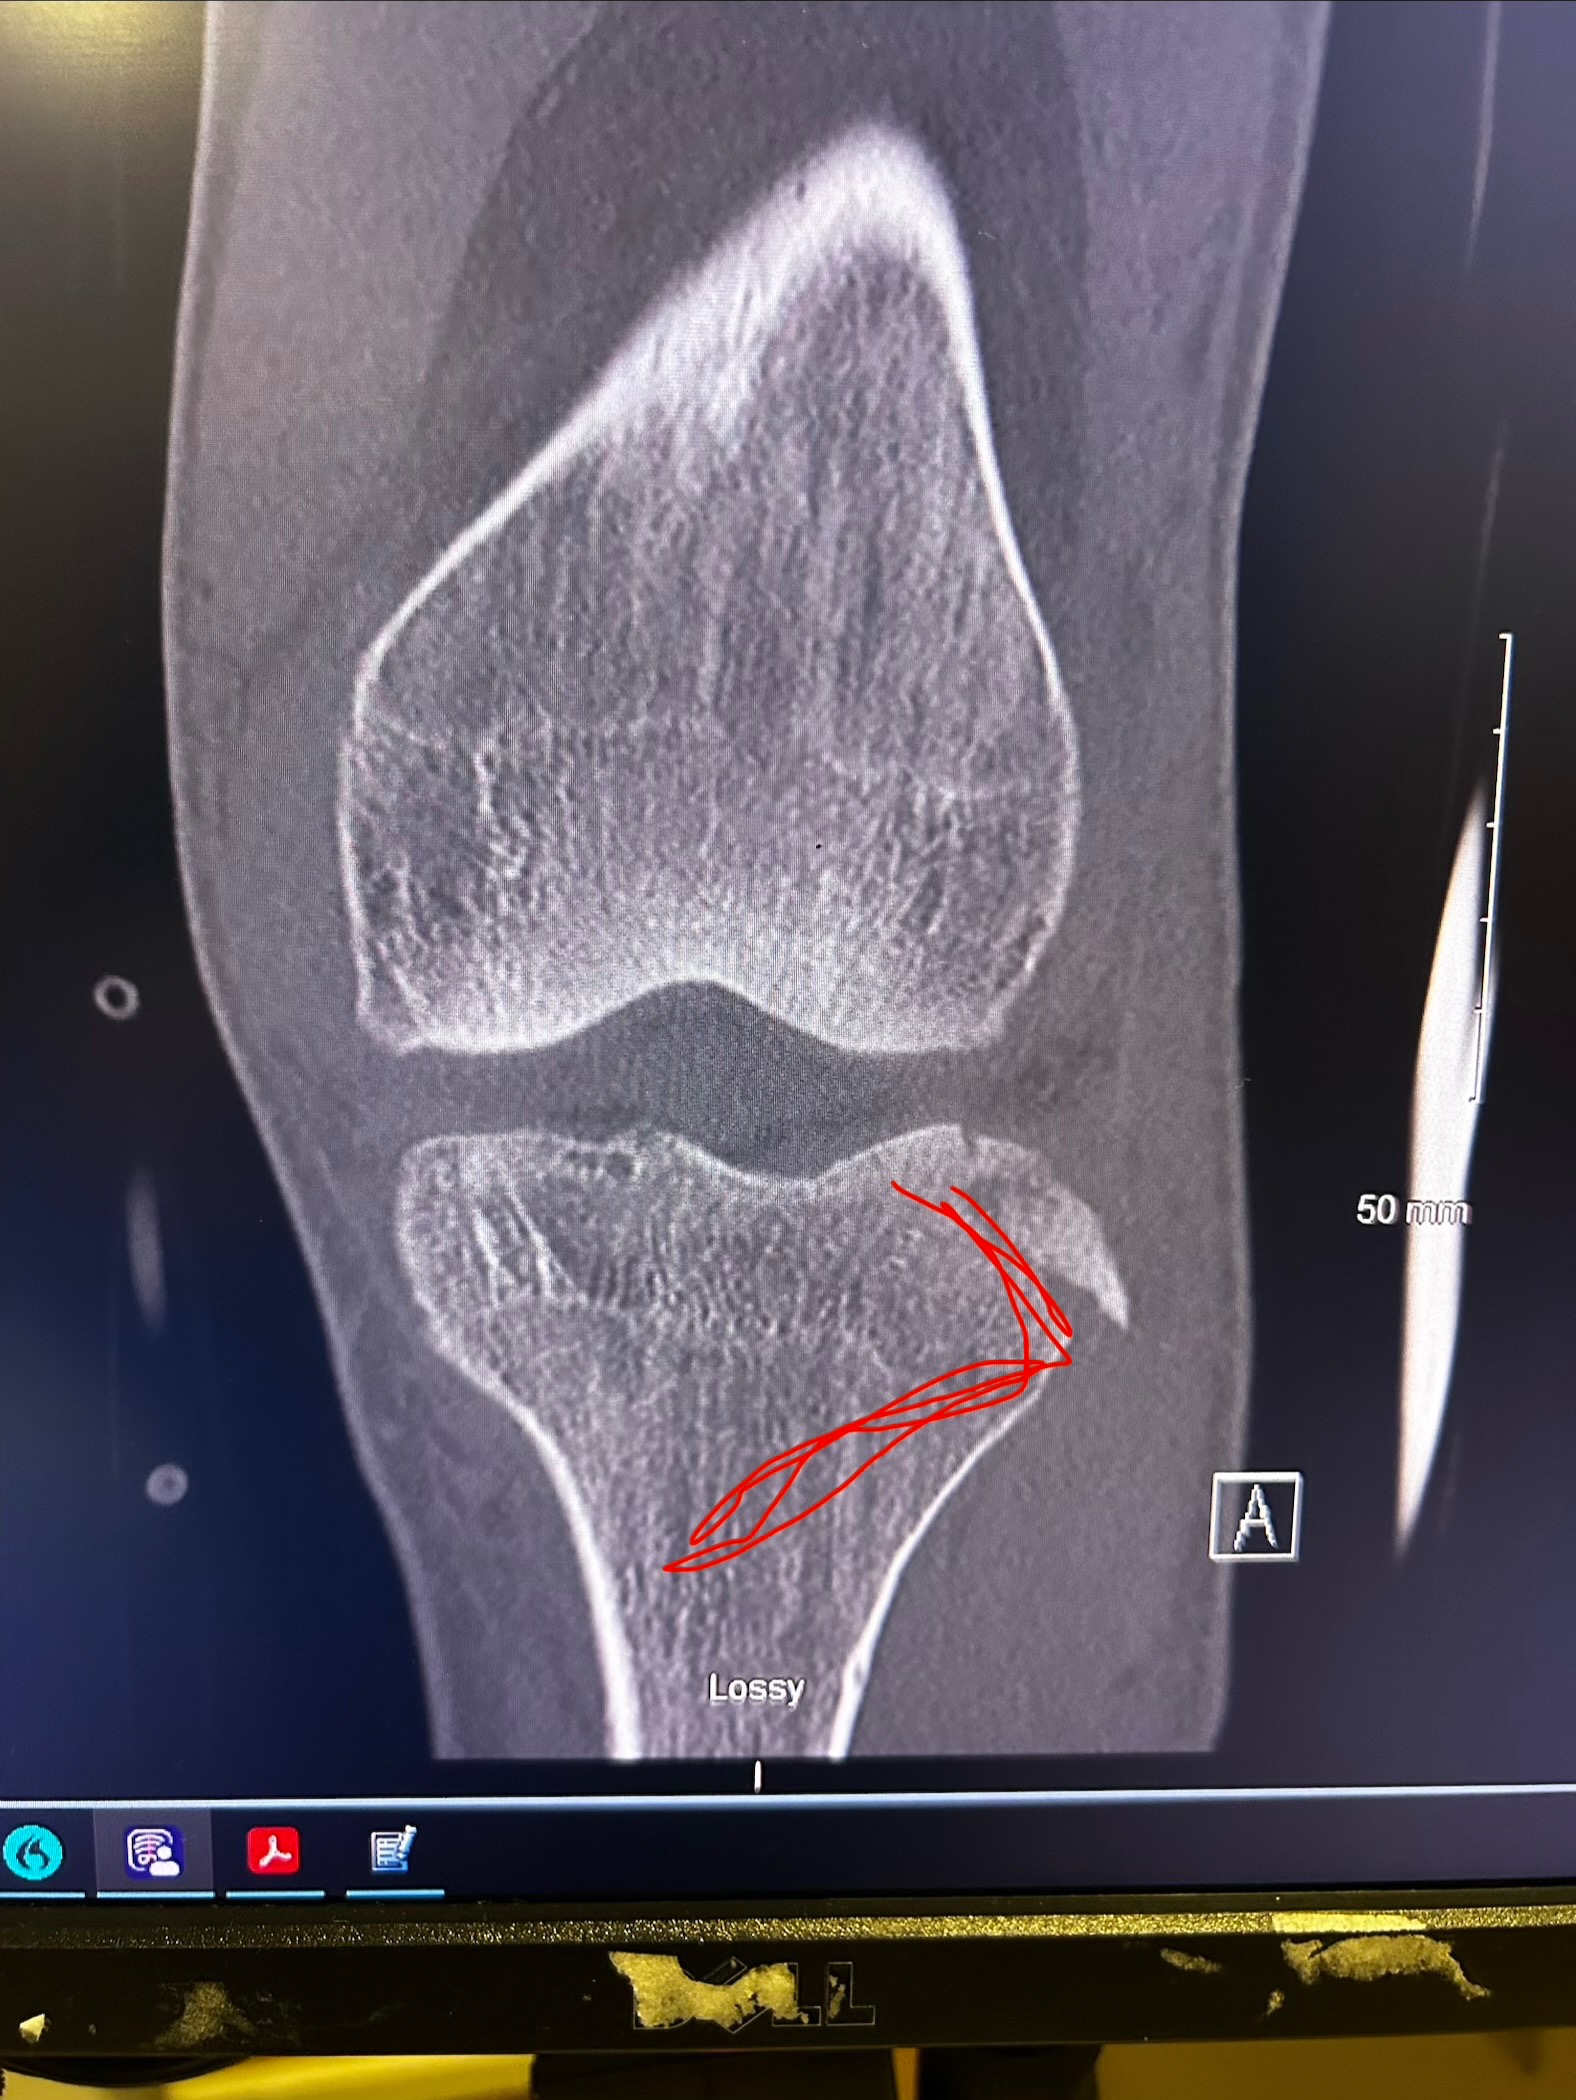

On January 22nd at 10:49 AM, I got the call no one ever wants to receive. It was John, screaming that he had fallen. In that moment, everything stopped. John fell approximately 20–25 feet, causing severe injuries from his left knee down. We are incredibly grateful and beyond blessed that he is alive today, because this situation could have ended very differently.